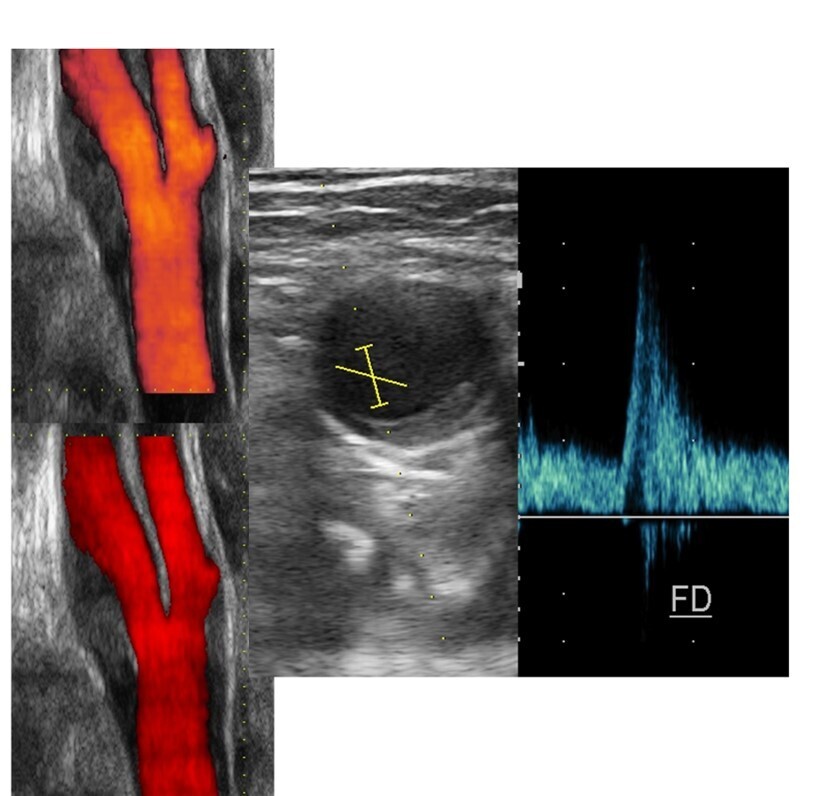

- * Les examens ultrasonographiques ont été réalisés par des échographistes expérimentés pour évaluer l'épaisseur des plaques.

Importance de l'Évaluation par Échographie

L'échographie est un outil de diagnostic essentiel pour évaluer le risque cardiovasculaire.

- * La mesure de l'épaisseur des plaques dans les vaisseaux superficiels est hautement reproductible.

- * La plaque carotidienne est un indicateur de risque accru d'ASCVD, même si elle est inférieure à 3 mm.

- * L'échographie est rapide, peu coûteuse et sans radiation ionisante, ce qui en fait un outil idéal pour la prédiction des risques.

Lz rôle prédictif des calcifications carotidiennes est reconnu vs CAC . Mais dans la pratique ces plaques carotidiennes ne suffisent pas à mon sens et j'ajoute les plaques du segment iliofémoral droit et gauche et les plaques au niveau de l'aorte sous-rénale. Enfin les calcifications mammaires sont aussi très utiles. Cette comptabilisation est simple, les plaques à retenir doivent être au minimum de 2 mm d'épaisseur . Dans la VRAIE VIE les patients concernés sont tous à haut risque CV. Il faut privilégier le NON INVASIF en prévention primaire ! Enfin ne pas oublier que tout cela doit être précédé de la correction "drastique" des FDRCV, sinon à quoi bon vouloir faire une prévention primaire. Evaluer le risque CV en prévention primaire, c'est aussi mesurer l'onde de pouls , l'épaisseur intima média et l'IPS de cheville. C'est ainsi que l'on peut détecter un risque CV significatif chez un patient jeune asymptomatique et alors prescrire une statine en fixant la cible LDL en tenant compte de tous ces paramètres. C'est cost-effective, c'est efficace, ça prend peu de temps et ainsi le cadrage vasculaire du patient est complet. La consultation cardiologique sera systématique.

Le FUTUR du FUTUR : l'écho-Doppler n'a pas encore atteint l'Intelligence Artificielle (IA) et c'est dommage. L'inertie des constructeurs vis à vis de l'IA est assez incompréhensible. La quantification de la sténose carotidienne pourrait bénéficier largement de l'IA. Les préoccupations actuelles en matière d'imagerie diagnostique concerne le scanner et l'IRM . L'évolution IA des ultrasons concernent la mise au point d'appareils pilotés par l'IA et utilisable par des non médecins. Ces appareils sont focalisé par exemple sur une mesure comme la fraction d'éjection du ventricule gauche ou le repérage d'une thrombose veineuse.